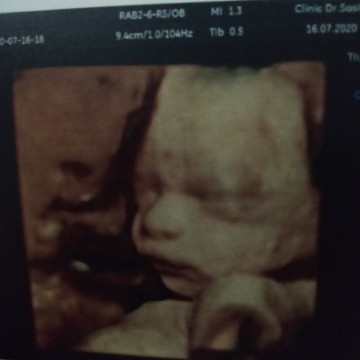

จมูกพุ่งจังลูก

😍😍😍😍😍😍